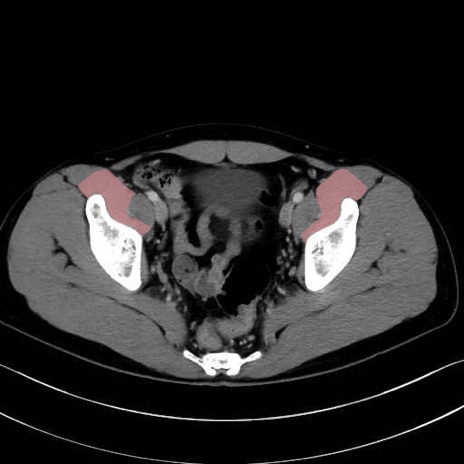

腸骨筋 (Iliacus)